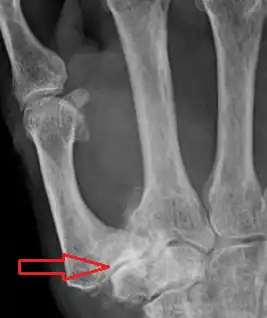

![]() Imagen radiográfica que muestra signos de artrosis de la articulación trapeciometacarpiana. | ||

Dentro de las pruebas radiológicas, la que ofrece mayor fiabilidad para el diagnóstico de rizartrosis es la radiografía. Las formas de posicionamiento estándar de esta incluyen la vista postero-anterior, lateral y oblicua. Sin embargo, aunque estas posiciones permiten diagnosticar rizartrosis de forma fiable, ninguna de ellas permite evaluar la evolución de los cambios artrósicos en la articulación. La posición de Gedda, realizada mediante una rotación externa de la muñeca y la colocación de la mano en posición oblicua respecto a la placa radiográfica, permite una mayor fiabilidad a la hora de evaluar la situación del espacio intraarticular de la articulación trapeciometacarpiana, pero la dificultad a la hora de colocar la mano del paciente en esta posición hace que no se trate de un método estandarizado.[22][23][24]

La más utilizada es la clasificación de Eaton, basada en las características radiográficas de la articulación.